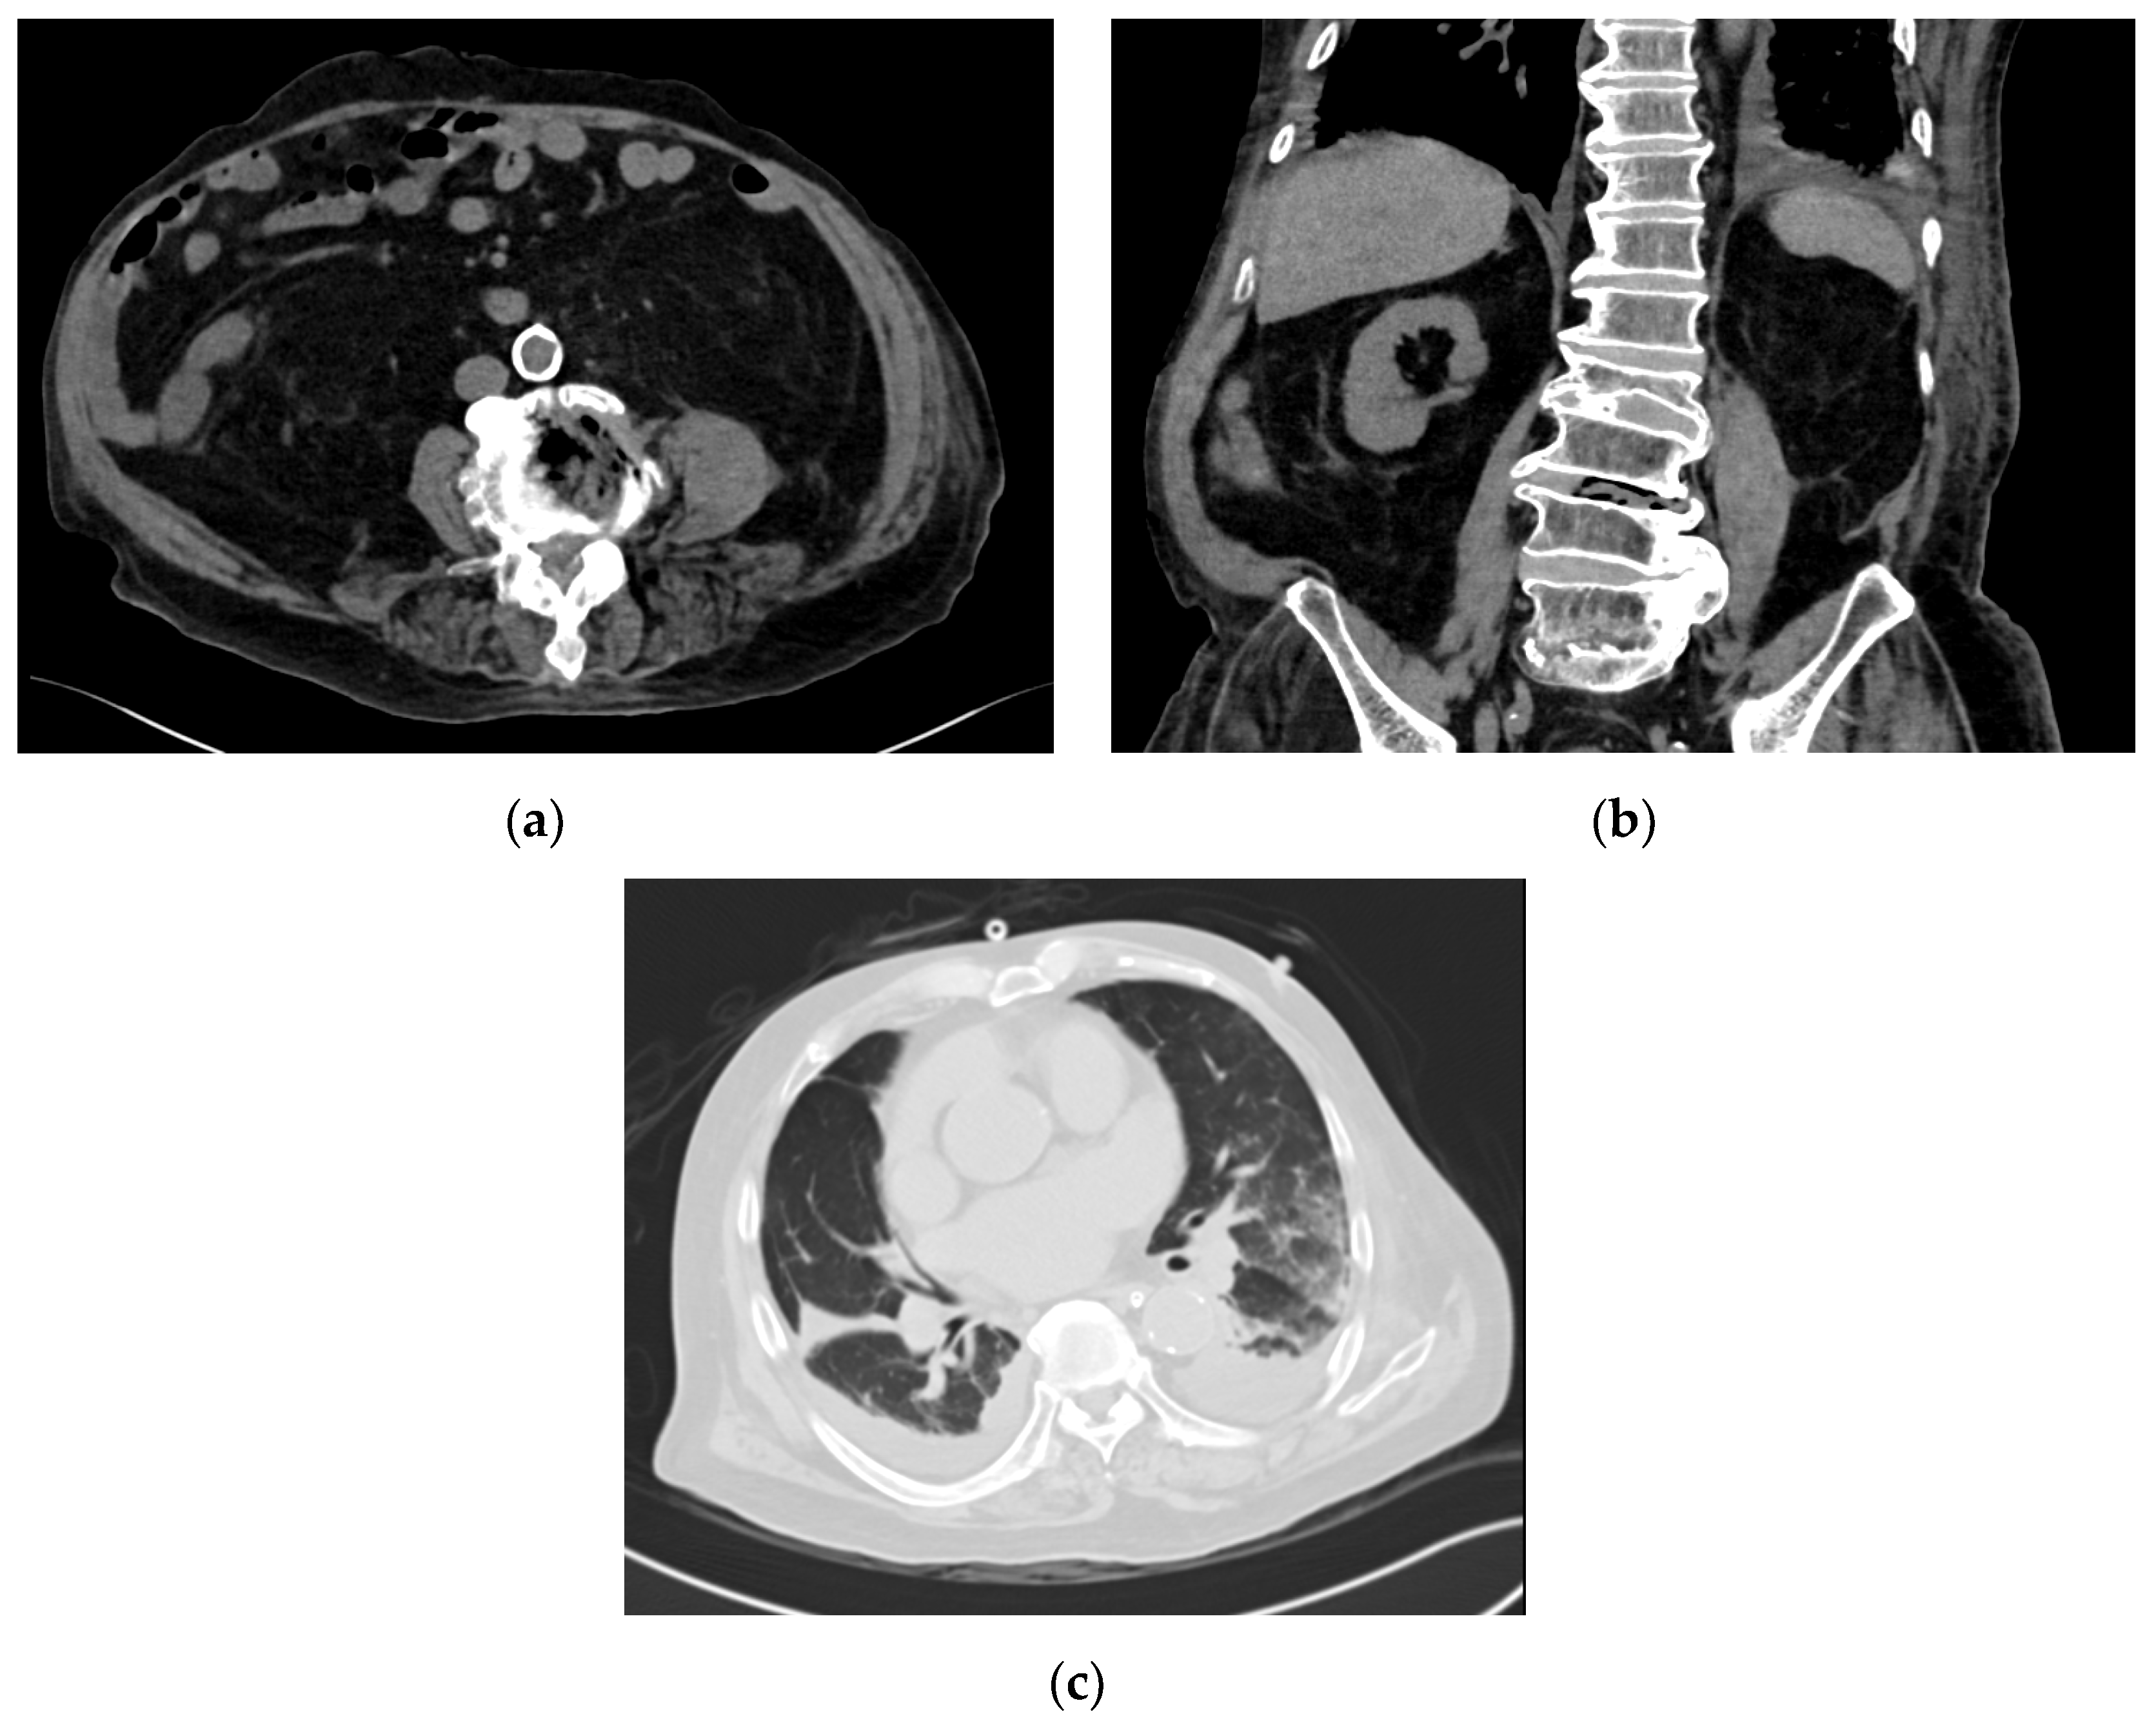

On the fifth day of hospitalization, magnetic resonance imaging (MRI) of the brain demonstrated ventriculitis. There was no evidence of brain abscesses. On the seventh day of hospitalization, in view of persistent pyrexia, a computed tomography (CT) scan of the thorax, abdomen and pelvis was performed, which showed gas locules within the L3/L4 intervertebral disc with asymmetric thickening of the left psoas muscle, suggestive of a psoas abscess and concurrent spondylodiscitis (Figure 1a,b). There were also bilateral patchy airspace changes and moderate pleural effusions suggestive of pneumonia (Figure 1c) and small pericardial effusion. The transthoracic echocardiogram was negative for vegetations. In view of the prolonged hospitalization and persistent fever, his antibiotic coverage was changed to IV cefepime, metronidazole and ampicillin, to provide broader empiric nosocomial cover. Repeated blood cultures remained negative. An MRI scan of the lumbar spine showed left psoas myositis with phlegmon and small gas-containing abscesses. However, as the abscesses were small and the patient was coagulopathic, drainage of the abscesses was deemed infeasible.

Figure 1.

Strongyloides hyperinfection associated with gas-forming spondylodiscitis and E. faecalis bacteremia. (a) Transverse view of the computed tomography scan of the abdomen, demonstrating gas-forming spondylodiscitis. (b) Coronal view of the computed tomography scan of the abdomen, demonstrating gas-forming spondylodiscitis. (c) Bilateral pulmonary infiltrates noted on the computed tomography scan of the thorax.